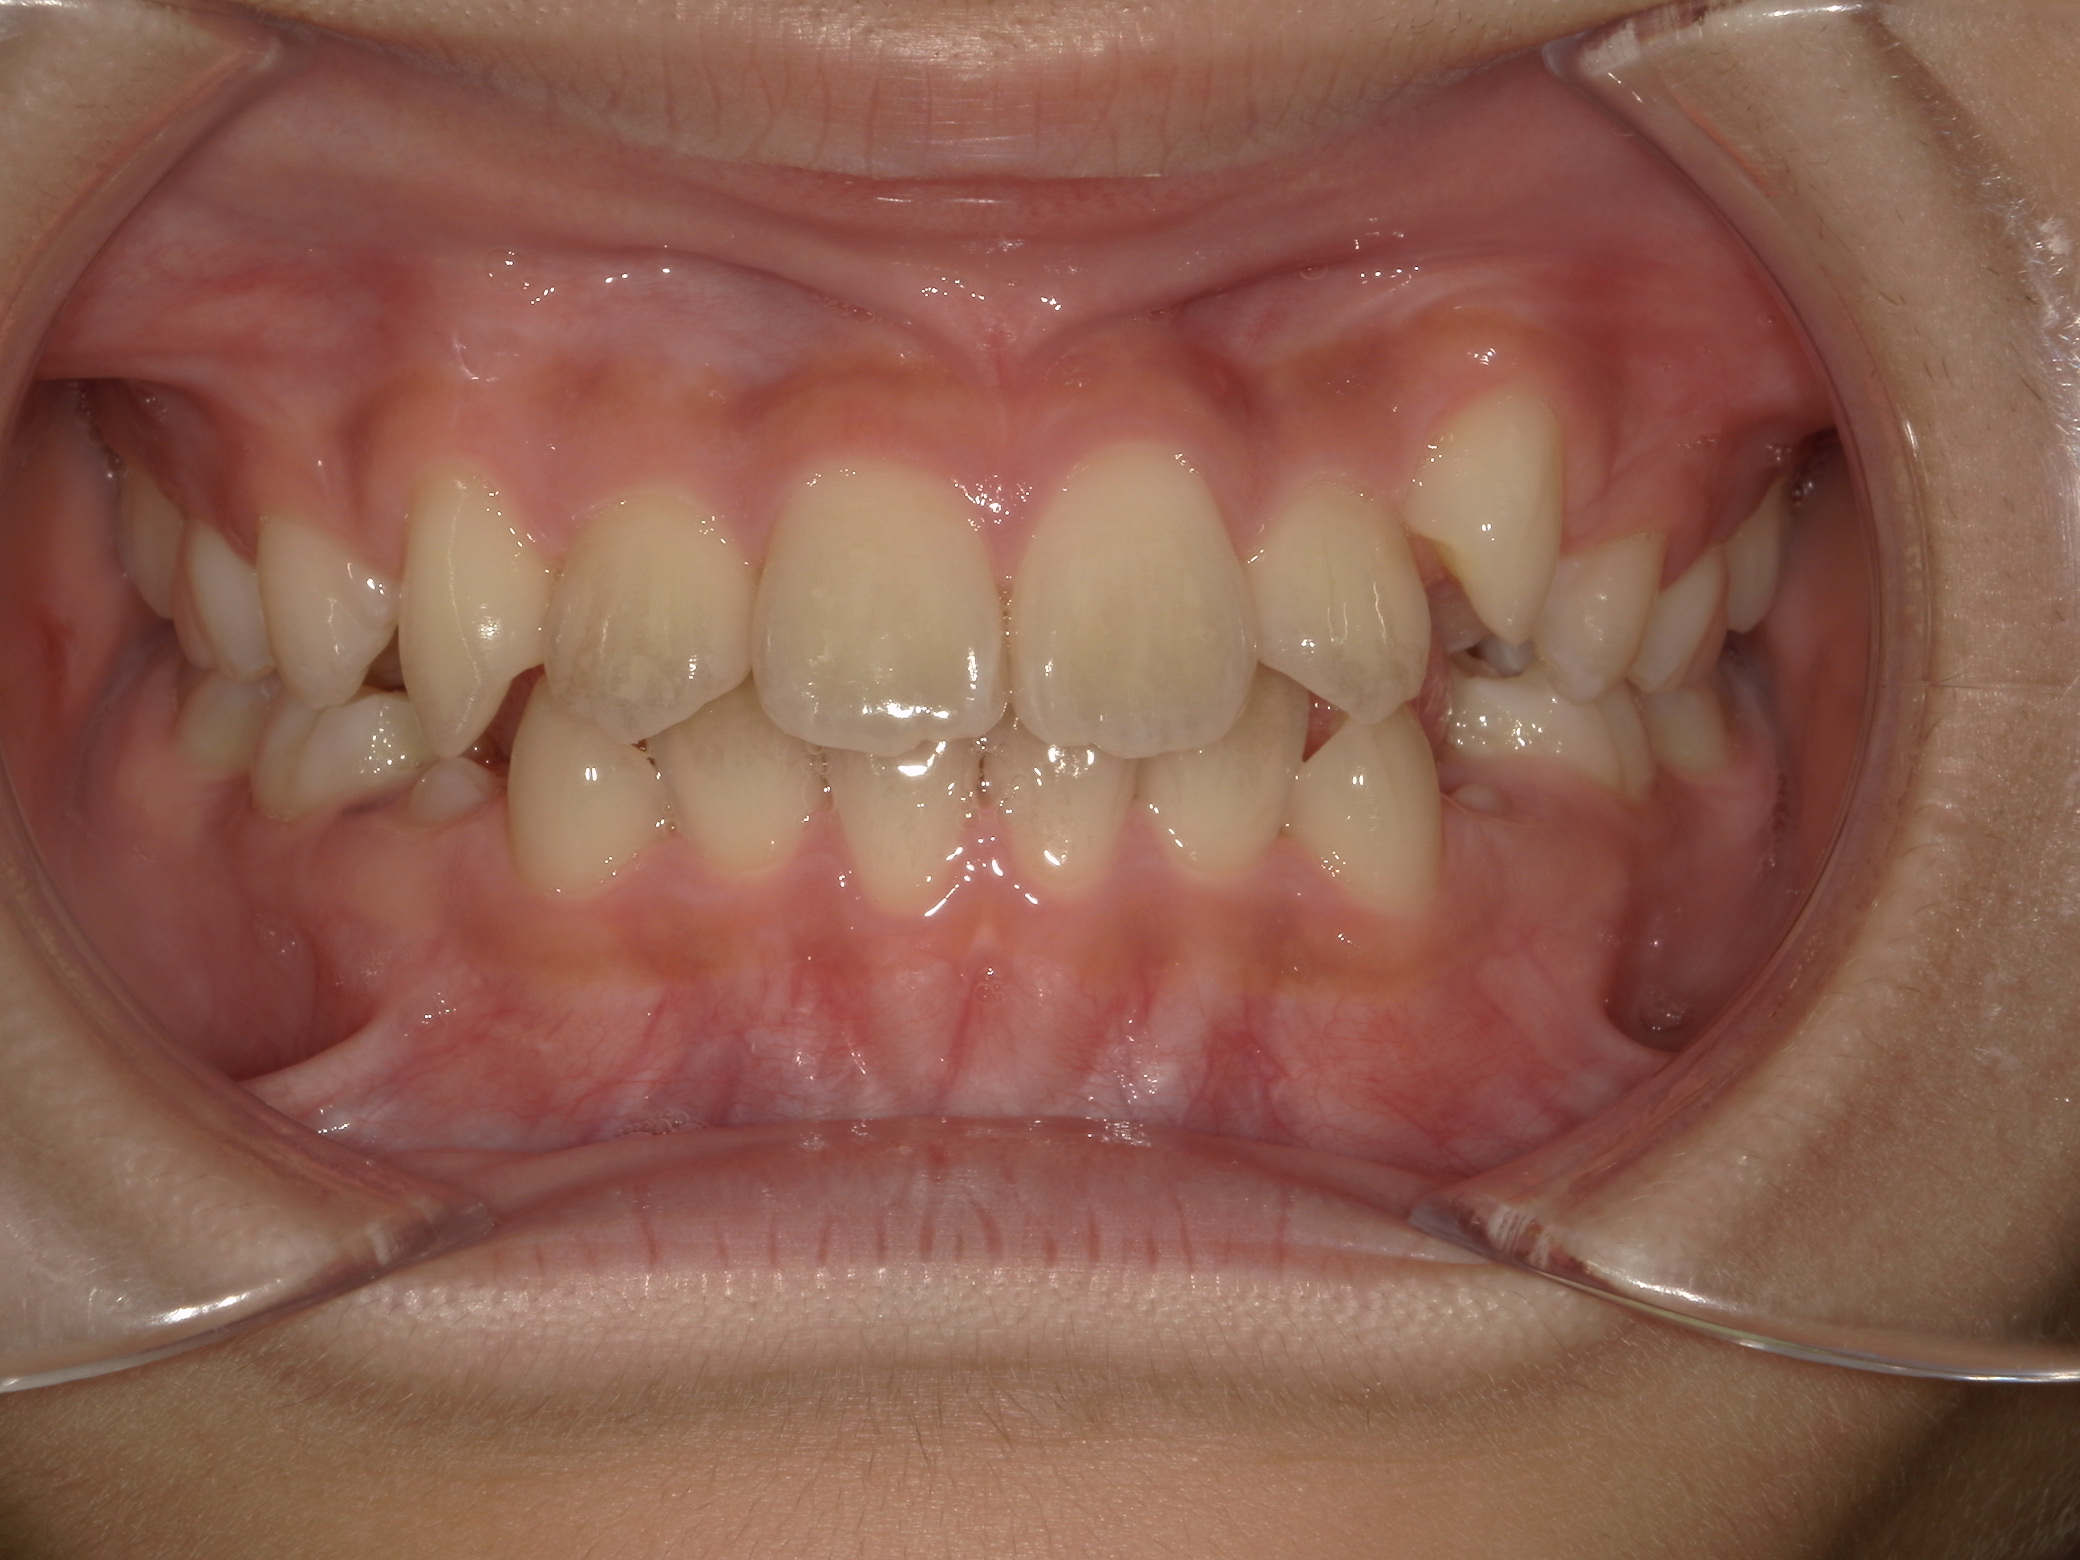

すきっ歯

7歳 女性

プレオルソによる筋機能訓練(MFT)

筋機能トレーナー(プレオルソ)

495,000

約1年

舌癖による不正咬合が認められたため、プレオルソを使用して口腔周囲筋のバランスを整え歯並びが改善しました。

患者様の使用協力が得られれば、プレオルソのみで綺麗な歯並びにすることが可能です。歯の位置異常がないかなどのきちんとした矯正精密検査、矯正医の診断のもと装置の選択を行うことが大切です。

リスク:歯肉退縮、歯根吸収、後戻り、予期せぬ成長